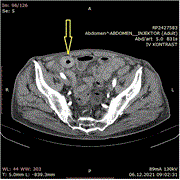

Isolated free intraperitoneal fluid in young male after blunt abdominal sport trauma: two case reports from the World Cup 2022

Abubaker Al-Aieb and others

Journal of Surgical Case Reports, Volume 2023, Issue 10, October 2023, rjad561, https://doi.org/10.1093/jscr/rjad561